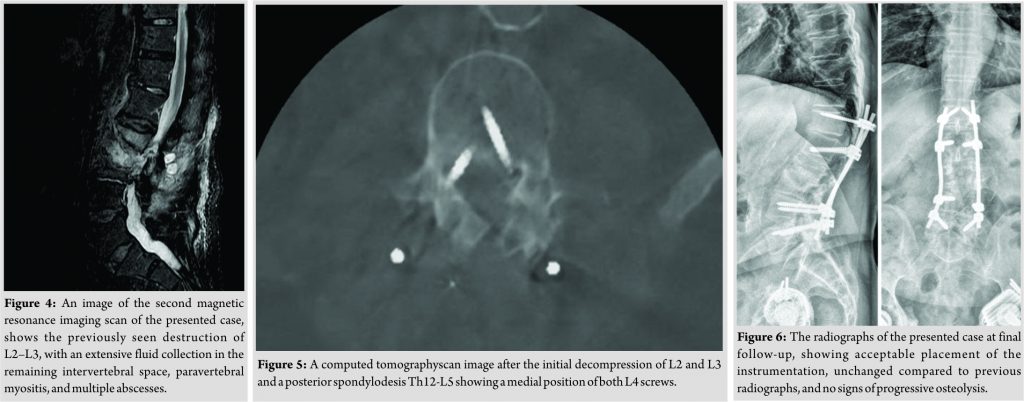

A 78-year-old male patient was referred to our tertiary, university hospital outpatient clinic with pain in his right leg. His medical history included a laminectomy of L3-L5, performed 1.5 years before his current visit, because of spinal stenosis as a result of degenerative scoliosis. This procedure was followed by the collapse of the vertebral bodies of L2 and L3 with compression of the right nerve root and spinal stenosis at L3. There had not been any wound problems or other complications after the first procedure. Further medical history included bilateral total hip arthroplasty, revision of the left hip arthroplasty after 19 years, left total knee arthroplasty, hypertension, and ulcerative colitis (without medication). The physical examination showed a lumbar scoliosis with a painful and slightly reduced range of motion of the spine whereas the sacroiliac and hip joints showed a pain-free and normal range of motions. The knee and Achilles tendon reflexes were lower on the right side. Sensation and motor function were normal. The radiographs (Fig. 1) and magnetic resonance imaging (MRI)(Fig. 2) showed degenerative scoliosis with the apex on L2-L3 with the collapse of the vertebral bodies of L2 and L3. Serum markers for infection, 2 months before the presentation at our clinic, were as follows: C-reactive protein (CRP) <1 mg/L, leukocytes 8.8 × 10 e9/L, and erythrocyte sedimentation rate (ESR) 12 mm/h. To exclude a possible spondylodiscitis, as a cause of the sudden vertebral body collapse a positron-emission tomography-computed tomography scan was performed, which showed no clear signs of infection but severe degeneration at level L2-L3 (Fig. 3). We planned a surgical decompression of L2-L3 on the right side with a posterior spondylodesis of L1-L5. During the ambulatory waiting time before surgery, the patient’s symptoms worsened. He was unable to walk and stand because of severe pain in the lumbar spine, without signs of neurological impairment. Four weeks before the onset of progressive symptoms, a broken molar was removed during a dental procedure. The patient interview revealed no alternative explanation for his worsening condition. He was admitted to the hospital, and the date of surgery was advanced. Serum infection markers showed a CRP of 174 mg/L, leukocytes of 11.9x10e9/L, and ESR of 128 mm/h. A new MRI scan showed the previously seen destruction of L2-L3, with an extensive fluid collection in the remaining intervertebral space, paravertebral myositis, and multiple abscesses (Fig. 4). Based on the new clinical situation, a decompression of L2 and L3 and a posterior spondylodesis T12-L5 was performed obtaining deep cultures of tissue and the abscess in the disc space. Vancomycin and ciprofloxacin were started postoperatively. Weakness of the right quadriceps was observed in the first postoperative hours, and a CT-scan (Fig. 5) showed a medial position of both L4 screws. These were replaced by using a revision procedure in the same day. Unfortunately, the weakness persisted in the following weeks. All intraoperative cultures showed P. micra, and the antibiotic treatment was changed to penicillin intravenously (12 g daily) based on the sensitivity spectrum. The pain and infectious signs subsided, and the serum infection markers improved after 2 weeks of antibiotics as follows: CRP 43 mg/L and leukocytes 9.3 × 10 e9/L. The antibiotic treatment was continued orally with clindamycin (600 mg three times daily) for 4weeks. At the last visit to the outpatient clinic, at 1year after surgery, the patient reported only occasional back pain. Blood results as follows: CRP 8 mg/L, leukocytes 8.6 × 10e9/L, and ESR 32 mm/h. Radiography of the spine (Fig. 6) showed unchanged spinal instrumentation and no signs of spondylodiscitis relapse.